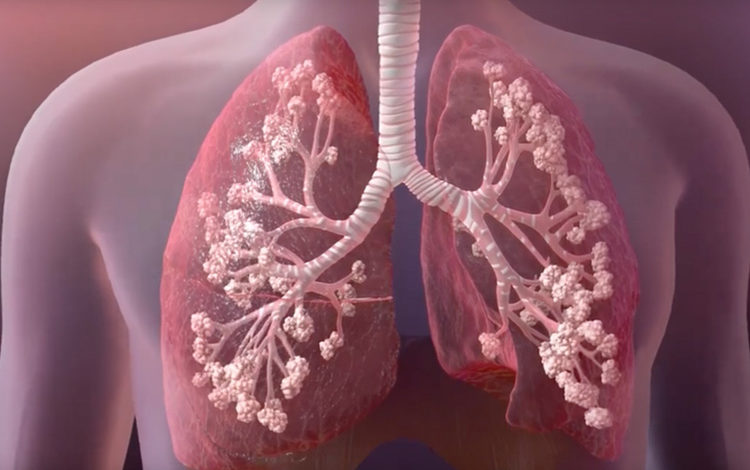

Kistik Fibrozis’in beyaz ırkta en sık görülen ölümcül genetik hastalık olduğuna özellikle dikkat çeken Çocuk Göğüs Hastalıkları Uzmanı Prof. Dr. Bülent Karadağ, “Başta solunum sistemi olmak üzere, sindirim, üreme ve endokrin sistemlerini etkiler. Hastalığın nedeni salgı yapan hücrelerdeki klor transport sisteminin bozulmasıdır. Bunun sonucu olarak salgılar, bronş sıvılarında ter, yoğun ve çok tuzlu bir hale gelmektedir. Enfeksiyon gelişmesi kolaylaşırken, bağırsaklarda ise enzimler salınamamakta ve yağ emilimi bozulmaktadır.” diye konuştu.

Hastalığın ilk görülen belirtilerinin; sık yağlı dışkılama, kilo alamama, inatçı düzelmeyen öksürük, tekrarlayan bronşiolitler ve özellikle sıcak bölgelerde terle tuz kaybından kaynaklanan vücuttaki su kayıpları olduğunu belirten Prof. Dr. Bülent Karadağ, “Hastaların yaşı ilerledikçe solunum bulguları belirginleşirken, kilo kayıpları ve düşük kiloda kalmaları dikkati çeker. Ergenlik döneminden itibaren pankreas hasarına bağlı diyabet, eklem problemleri, karaciğer hasarları ve kısırlık görülebilir.” dedi.